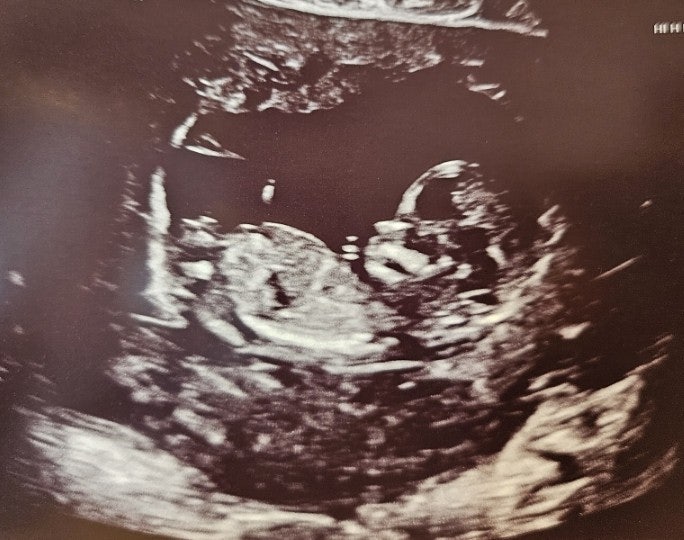

임신 중기 14주 15주 16주 성별 확인 영양제 바꾸기

벚꽃놀이 잘 다녀 오셨나요? 이번 봄은 살짝 늦게 찾아와준 것 같아요 그래도 4월 되고 따뜻한 봄을 잘 즐...

임신 초기 10주 11주 12주 13주 입덧 지옥 1차 기형아 검사 목투명대

벌써 임신 13주차 중기가 시작되었다. 임신초기 잘 지내온 나를 칭찬한다. 6주 심장소리 들은 후부터 시작...